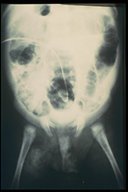

Plain X-ray shows the catheter inside the peritoneal cavity

Contrast filled through the catheter into the intestine - patent vitelline duct